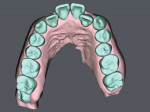

30-year-old female patient presented complaining of being embarrassed and insecure about her smile. Upon examination, the patient exhibited poor oral hygiene, bleeding, deep pockets, bone loss, and heavy subgingival and supragingival calculus. There was moderate-severe crowding in her maxillary arch with severe anterior cross-bite on teeth Nos. 7 and 10. A comprehensive treatment plan was presented and included stabilizing her periodontal condition and proceeding with SureSmile® Clear Aligners (Dentsply Sirona, suresmile.com) therapy. Clear aligner therapy was indicated over traditional brackets and wires due to hygiene concerns and the patient's existing periodontal condition. The case was completed with 35 aligners, attachments, and the adjunctive use of Chewies aligner tray seaters and SureSmile® VPro™, which were included in the SureSmile Complete package. The SureSmile aligner straight trimline design over the gingiva allowed for excellent traction and retention and minimal attachments. The patient experienced no gingival discomfort and tolerated the treatment well. Her smile was aligned to completion in 11 months with good traction and without refinement. The patient's periodontal condition and oral hygiene were improved with the overall effect of treating malocclusion. Today, the patient is proactive about her oral health, exhibits a confident, healthy smile, and is currently in retention therapy with SureSmile retainers.

SureSmile Clear Aligners therapy was able to predictably treat a moderate to severe anterior cross-bite case with minimal aligners and attachments, in a relatively short time period without refinement.